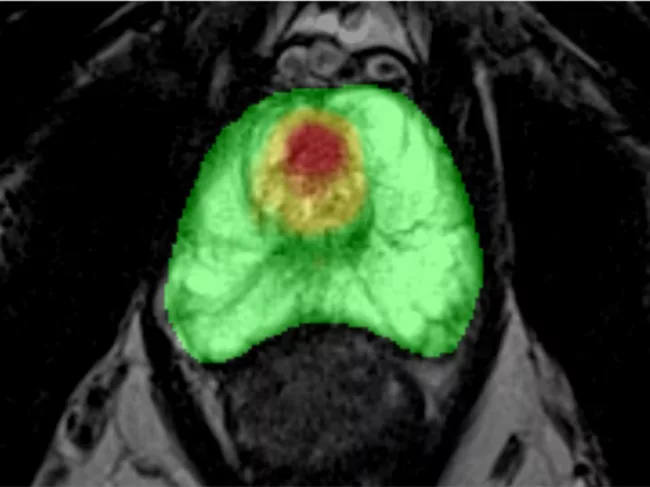

Enhanced MRI imaging using Prostatid.

Bot Image’s AI scores an FDA hat trick with clearance to diagnose, detect and monitor prostate cancer

The U.S. FDA gave Bot Image Inc. a coveted threefer with 510(k) clearance for its Prostatid artificial intelligence (AI) software for detection, diagnosis and monitoring of prostate cancer using both standard MRI and a non-invasive bi-parametric MRI, which does not require a contrast agent. Read More